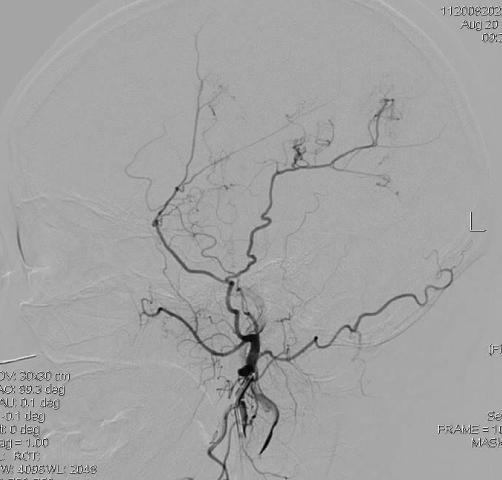

DSA显示右侧颈内动脉末端闭塞:

但是左侧是大脑中动脉闭塞: